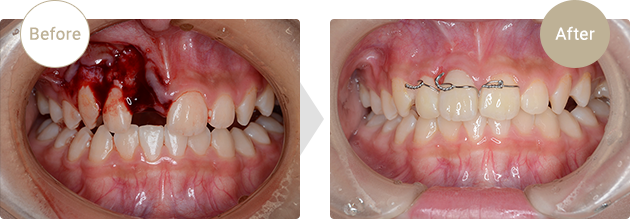

症例.02

歯の脱臼

転倒により上顎前歯脱臼及び裂傷。脱臼歯を修復し、ワイヤーにて整復固定しました。術後1ヶ月で回復しました。